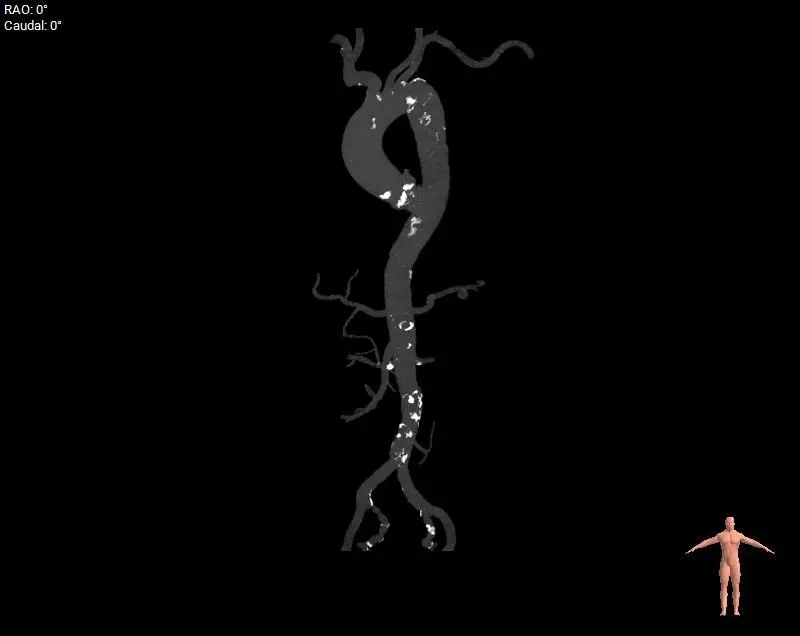

精析病例Ⅲ 心尖入路反流

主动脉根部测量

周长径28.8

周长径29.5

L:48.2 N:47.3 R:24.8

周长径45.4

周长径45.5

L:28.1 N:27.3 R:24.5

-

三叶式主动脉瓣

流出道敞口

瓦氏窦、升主扩张

瓣叶轻微增厚

瓣上结构测量

周长径28.6

周长径29.9

周长径31.5

周长径33.8

周长径35.4

周长径35.8

瓣上空间逐渐增大,瓣上瓣叶轻微增厚,0-6mm可提供锚定力

外周入路评估

外周血管无明显病

66°横位心

麻醉方式:全身麻醉

冠脉风险:低

球囊扩张策略:不预扩

瓣膜型号:ScienCrown TAVTF32mm(oversize11.1%)

入路选择:经心尖入路(患者横位心,根部明显扩张故选择心尖入路)

手术操作:该患者流出道敞口型,流出道无锚定力,瓣上空间扩张,需充分利用瓣环锚定;同时瓣膜横位心验证,术中需充分利用瓣膜全可回收功能,评估瓣膜稳定性